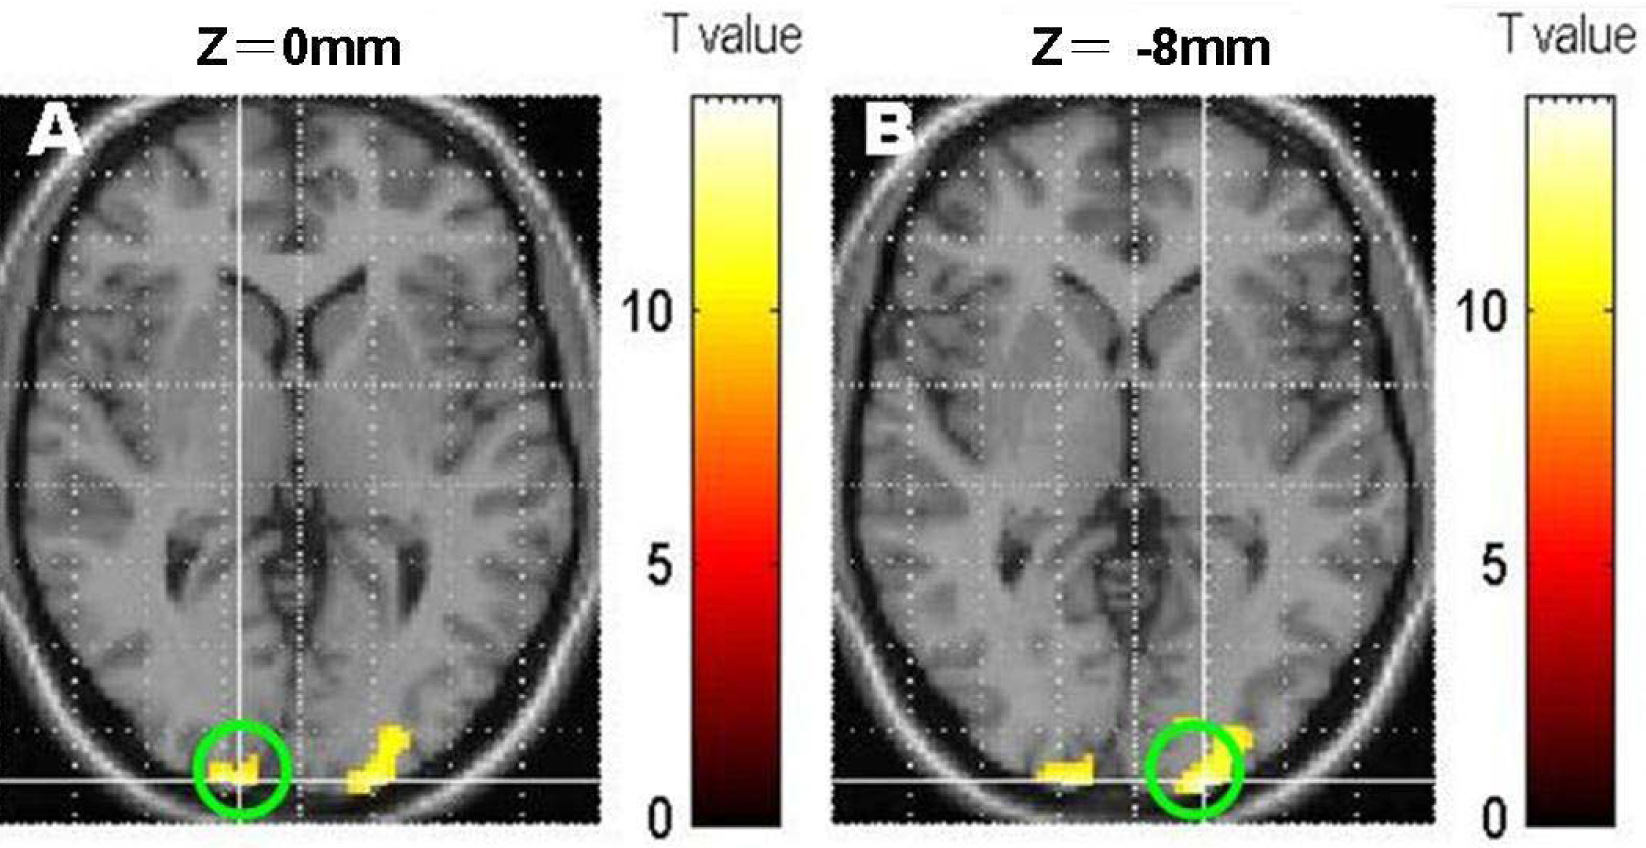

Figure 2 of Wang, Mol Vis 2012; 18:909-919.

Figure 2. Drawing of the regions of interest. A: Homonymous cortex of Brodmann areas (BA) 17; B: contralateral cortex of BA 17; the green circle labeled the regions of interest (ROIs).